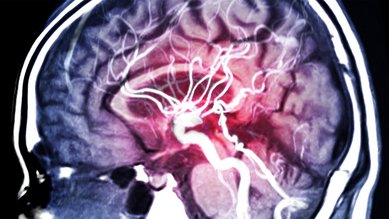

Menschliches Gehirn im Querschnitt: Blutgefäße und Hirnschlagader sind sichtbar. Menschliches Gehirn im Querschnitt: Blutgefäße und Hirnschlagader sind sichtbar.

Hirnaneurysma

Ein Hirnaneurysma ist eine Ausbuchtung einer Schlagader im Gehirn. Oft bleibt das unbemerkt und ohne Beschwerden. Reißt das Aneurysma, kommt es zu einer lebensbedrohlichen Hirnblutung.